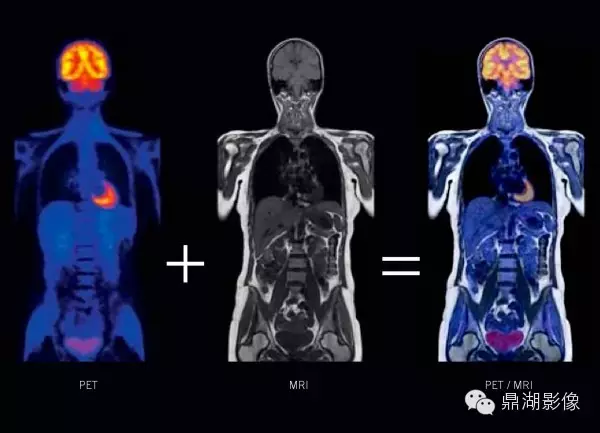

4.PET—MRI设备:PET-MRI是将PET(正电子发射计算机断层显像)的分子成像功能与 MRI (核磁共振成像)卓越的软组织对比功能结合起来的一种新技术。

一体化PET—MRI是将PET和MRI有机组合在同一个机架内,在MRI变化不大的前提下,重新设计PET探测器以适应MRI的高磁场、高射频场和高梯度切换,将PET探测器集成在MRI的射频体线圈和梯度线圈之间,一次扫描即可同时完成PET和MRI检查,可获得人体有关解剖、PET/MRI检查与其他手段相比,它的灵敏度高、准确性好,对许多疾病(尤其是肿瘤和心脑疾病)具有早期发现、早期诊断的价值。

这是一例PET-MRI诊断的盲肠炎患者,在融合后发现盲肠区域有小片状的炎症性改变,但在独立的MRI图像和FDG-PET图像上很难显示。

Images provided by Drs. Alex Guimaraes, Ciprian Catana, Bruce Rosen, and David Berger (Massachusetts General Hospital, Boston, MA).